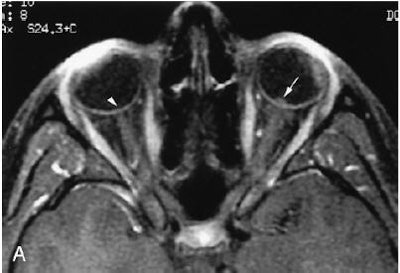

| Seventeen-year-old girl with moderate imaging findings of optic neuropathy due to cat scratch fever. Axial (A) and coronal (B) gadolinium-enhanced, fat-suppressed, T1-weighted images (TR1, Tr2/TE, 735, 875/14) show bulging of the left optic disk (arrow in A) that is markedly less pronounced than that on the right (arrowhead in A). The associated enhancement at the left optic nerve-globe junction (arrow in A and B) is also markedly less extensive. Note that normal appearance of the optic nerve-globe junction region on the right (arrowhead in A and B). Schmalfuss IM, Dean CW, Sistrom C, Bhatti MT, "Optic Neuropathy Secondary to Cat Scratch Disease: Distinguishing MR Imaging Features from Other Types of Optic Neuropathies" (AJNR, 26:1310-1316, June/July 2005). |